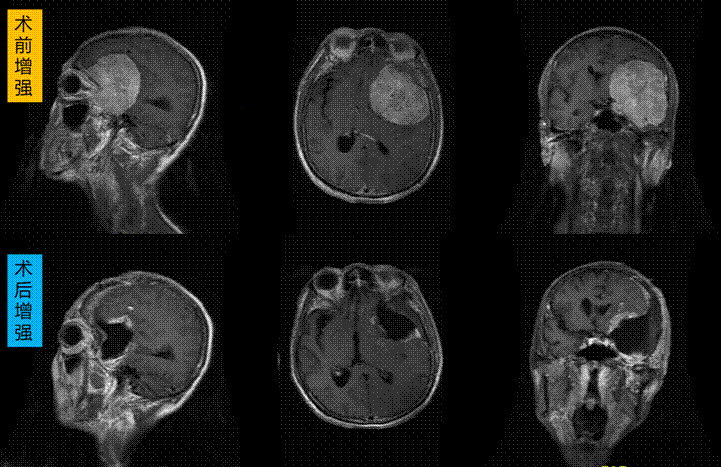

据主刀医生王宁主任介绍,焦大爷患有左侧蝶骨内侧型巨大多血性脑膜瘤,肿瘤最大经线达8cm,肿瘤内侧与颅内主要血管、视神经、海绵窦关系密切,切除较为困难,很可能造成神经功能缺失或脑梗死等并发症,严重者可危及生命。特别是患者比较瘦弱,血小板低、术前无法预存自体血,且新冠疫情之下血源极其紧张,即便省中心血站维持急危重患者供血都有一定困难,多种因素均加大了手术风险。最终王宁教授带领葛海涛副教授、鲁恩洲医师经过缜密研究决定为减少术中出血,对肿瘤组织术前行供血动脉栓塞,同时输注并补充血小板至正常范围,联系输血科备异体血,以备不时之需,术中精细操作止血、减少输血可能性。另一方案是与家属协商,若术中出血难以控制,且血液供应不上,可以行肿瘤部分切除,其余肿瘤考虑择期再进行手术全切。

在麻醉医生龚秀萍教授及器械护士孙宽、李雪的配合下,手术如期紧张有序的进行。据葛海涛副教授介绍,肿瘤较大、较韧且血供极其丰富,王主任每一步都快速、精细止血,最大限度的减少了患者失血。更为困难的是肿瘤中心钙化组织体积较大、坚硬如石,其深方与重要血管神经相粘连,只能跬步前行、一点一点分离,最终将钙化块切除腾出手术操作空间。然后分离瘤壁与周边脑组织及内侧主要血管、神经之间粘连,最终将肿瘤组织全部切除,瘤床完全显露,血管及神经无任何损伤。由于精细止血,手术耗时略长,但未输血、节约了用血,生命体征平稳,内环境稳定,顺利结束手术。